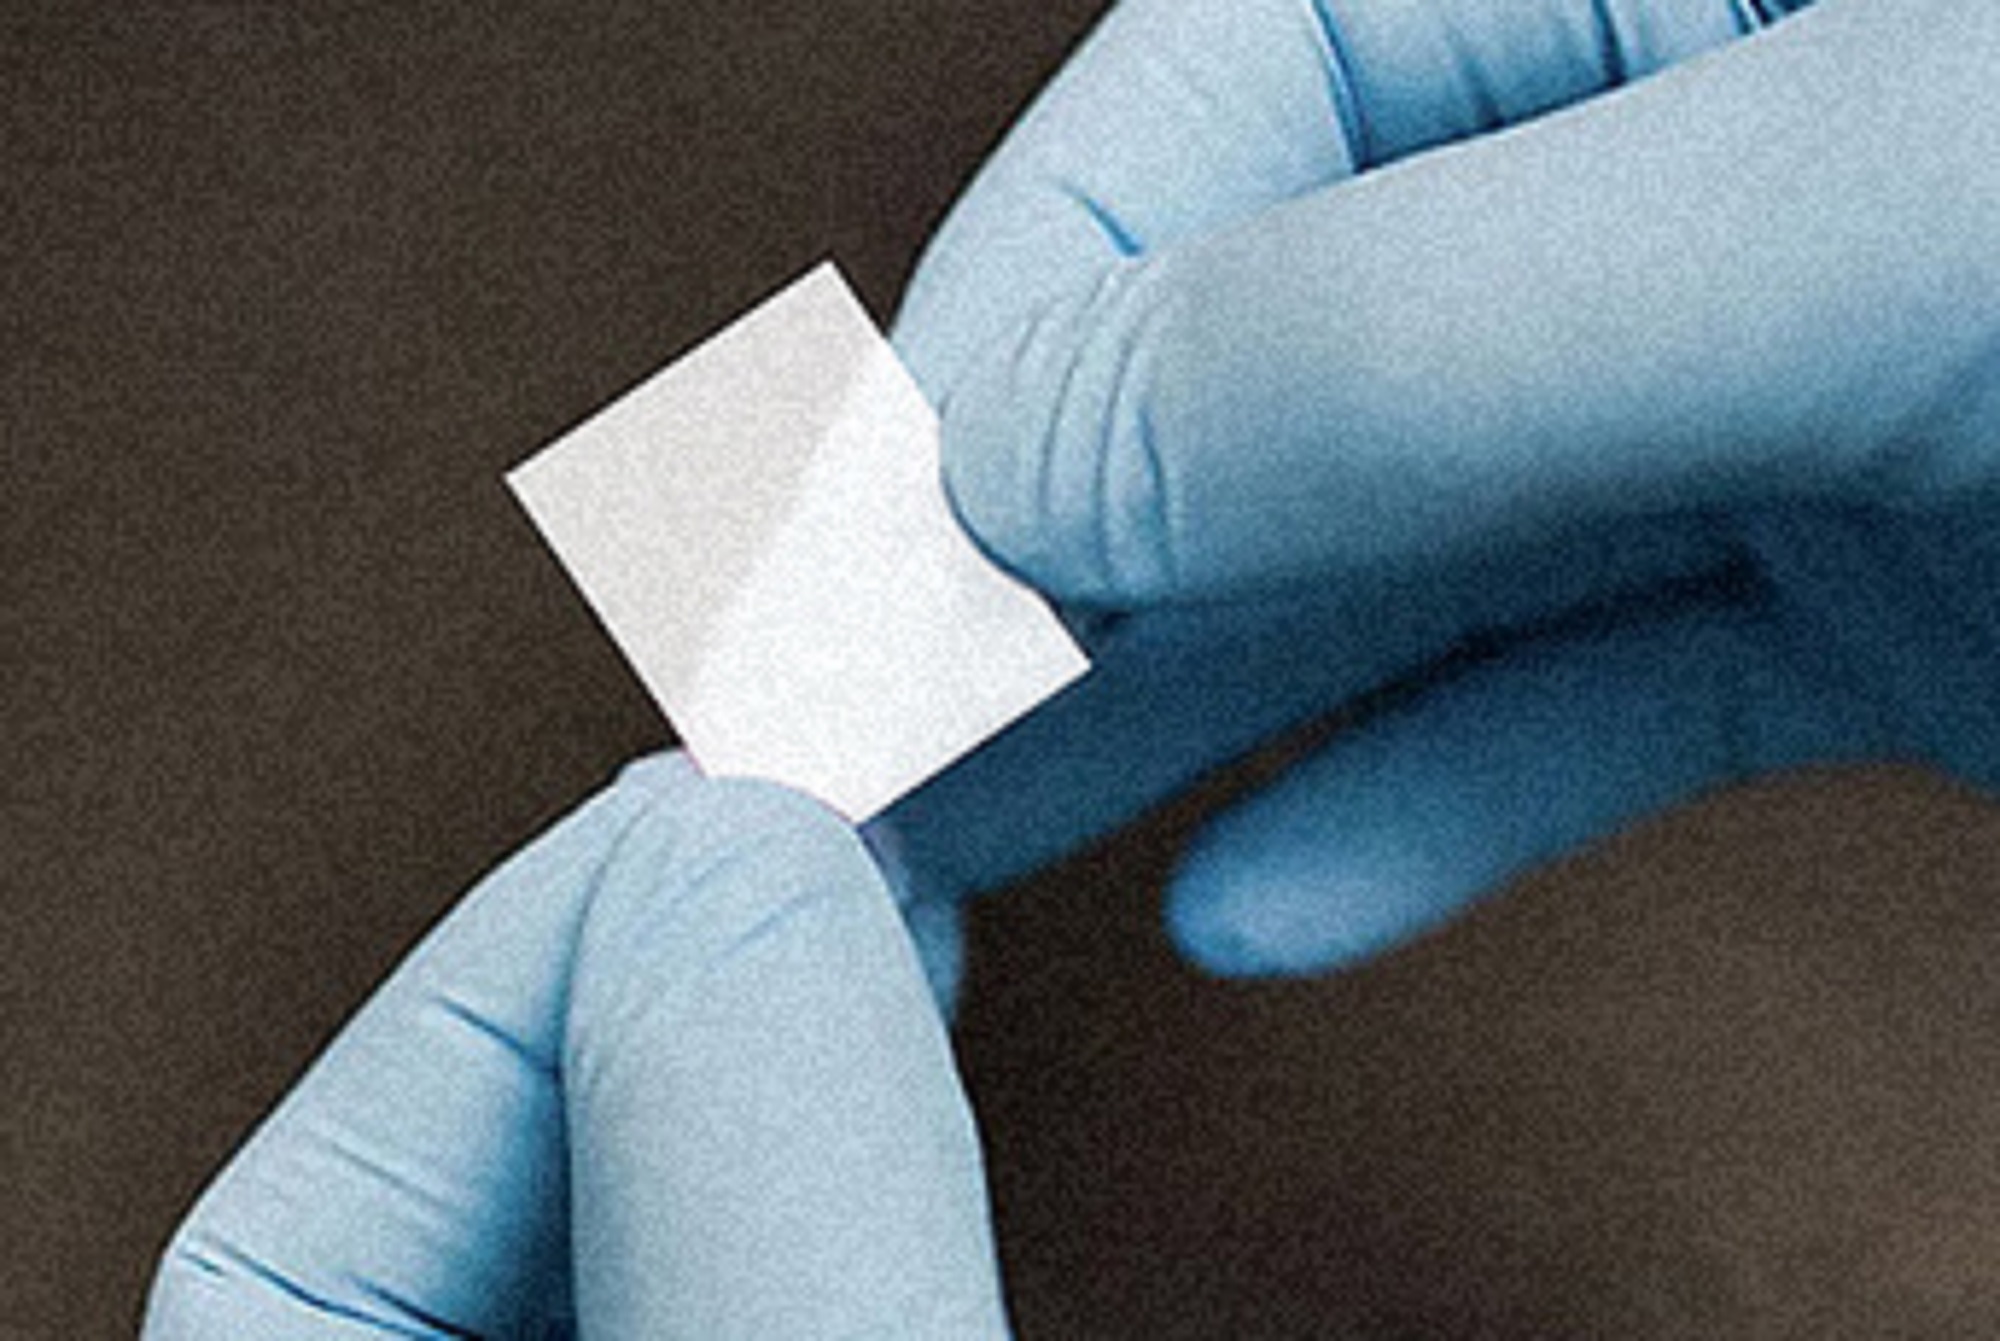

ODS (Orally Disntegrating Strips) are Fast Dissolving With Effective & Timely Delivery System, The Films Are Instantly Wettable, Rapidly Dissolving, Non-Sticky, Non-Tacky, And Non-Curving Is An Advantage Over Tablets & Capsules. No Water Required For Administrations.

Orally Disintegrating Strips (ODS), is A Novel Drug Delivery System Consists In A Very Thin Film Which Dissolves Quickly And Contains An Active Substance That Is Released In The Mouth (i.e On The Tongue). The Orally Disintegrating Strips (ODS) has Been Conceived to Accommodate a Wide Variety Of Active Substances For An Immediate Release on Or Under the Tongue Or On The Buccal Mucosa.

This method of medication has numerous advantages ranging from the patients to other factors. One of the very first reasons why oral films are considered more effective than other methods is that they take quick action and dissolve into the bloodstream in no time. Many other strips like B complex orally disintegrating strips focus on a healthy intake of vitamins.

Our Multivitamin orally disintegrating strips can be used by anyone irrespective of their age as it only requires placing the film under the tongue. Similarly, any precise dose can also be given conveniently through this process. If you have encountered any sort of oral medicine, you may already know the way it tastes. However, unlike traditional drugs, these films often taste like mint or have a subtle taste that does not seem odd.

Livkon Pharmaceuticals, one of the best ORO dispersible film manufacturers aims to help patients who have a tough time taking medicines. It is also a better option from the patient’s point of view as it prevents choking. Similarly, it also prevents the patient from rejecting the drug as no swallowing or chewing is involved. Many problems like bloating and inflammation and other problems can be easily solved with an orally disintegrating strip like Simethicone

One of the major benefits of orally disintegrating strips and thin films is that because it gets directly absorbed through the oral cavity, the drug involved with the film passes into the body through a passage called the GI tract. Because the components are sent down through this passage, it eliminates the effects, if any. Secondly, it also does not create gastric problems as seen with chewable tablets. In the same manner, a lot of other side effects as well are not triggered by consuming oral thin films.

Introducing Oral Thin Film Technology – a groundbreaking innovation in drug delivery systems. Designed for unparalleled convenience and efficiency, these thin, fast-dissolving films provide a modern solution to medication intake.

Revolutionizing Drug Delivery with oral thin film technology that offers unmatched convenience and effectiveness. These innovative films dissolve rapidly in the mouth, ensuring swift absorption into the bloodstream for immediate action.

No water is required, making them ideal for on-the-go lifestyles. Their fast-dissolving nature minimizes the risk of choking and provides a patient-friendly alternative to traditional tablets or capsules.

Orally Disintegrating Strips are thin films designed to dissolve rapidly in the mouth without the need for water. They provide a fast, effective, and convenient way to deliver medication or nutrients directly into the bloodstream.